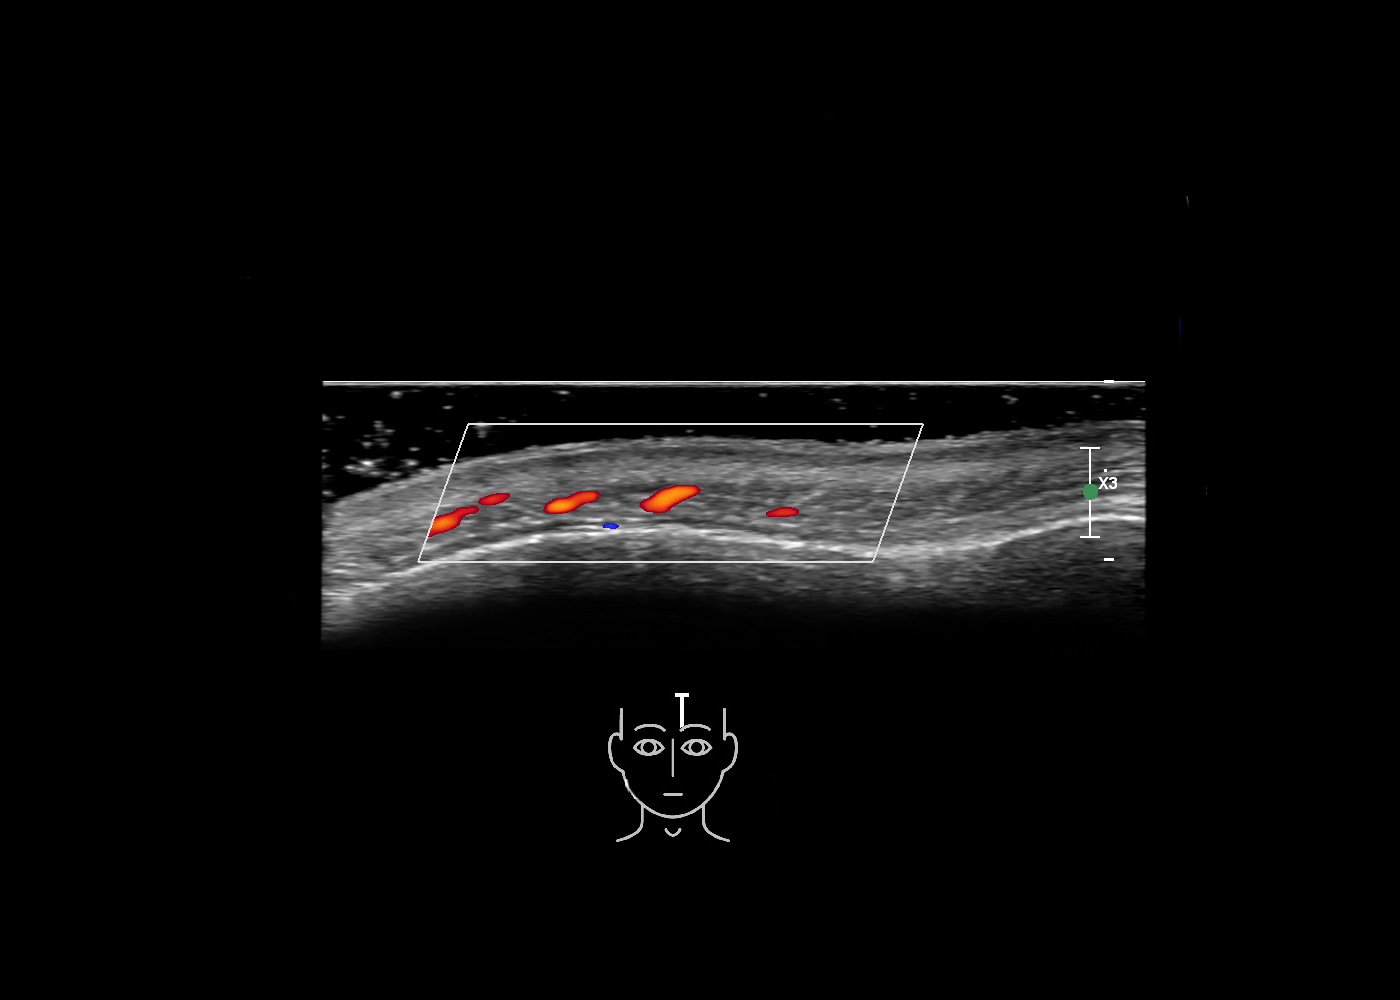

In this section you will learn more about the different layers of the face with the use of ultrasound. When you click on the secondary ultrasound image, you will see the different structures as an overlay. This will help to train yourself to recognize the different layers of the face.

Study the first image to recognize the different layers. If you are sure about the layers, swipe to the second image to view the answer (if applicable).